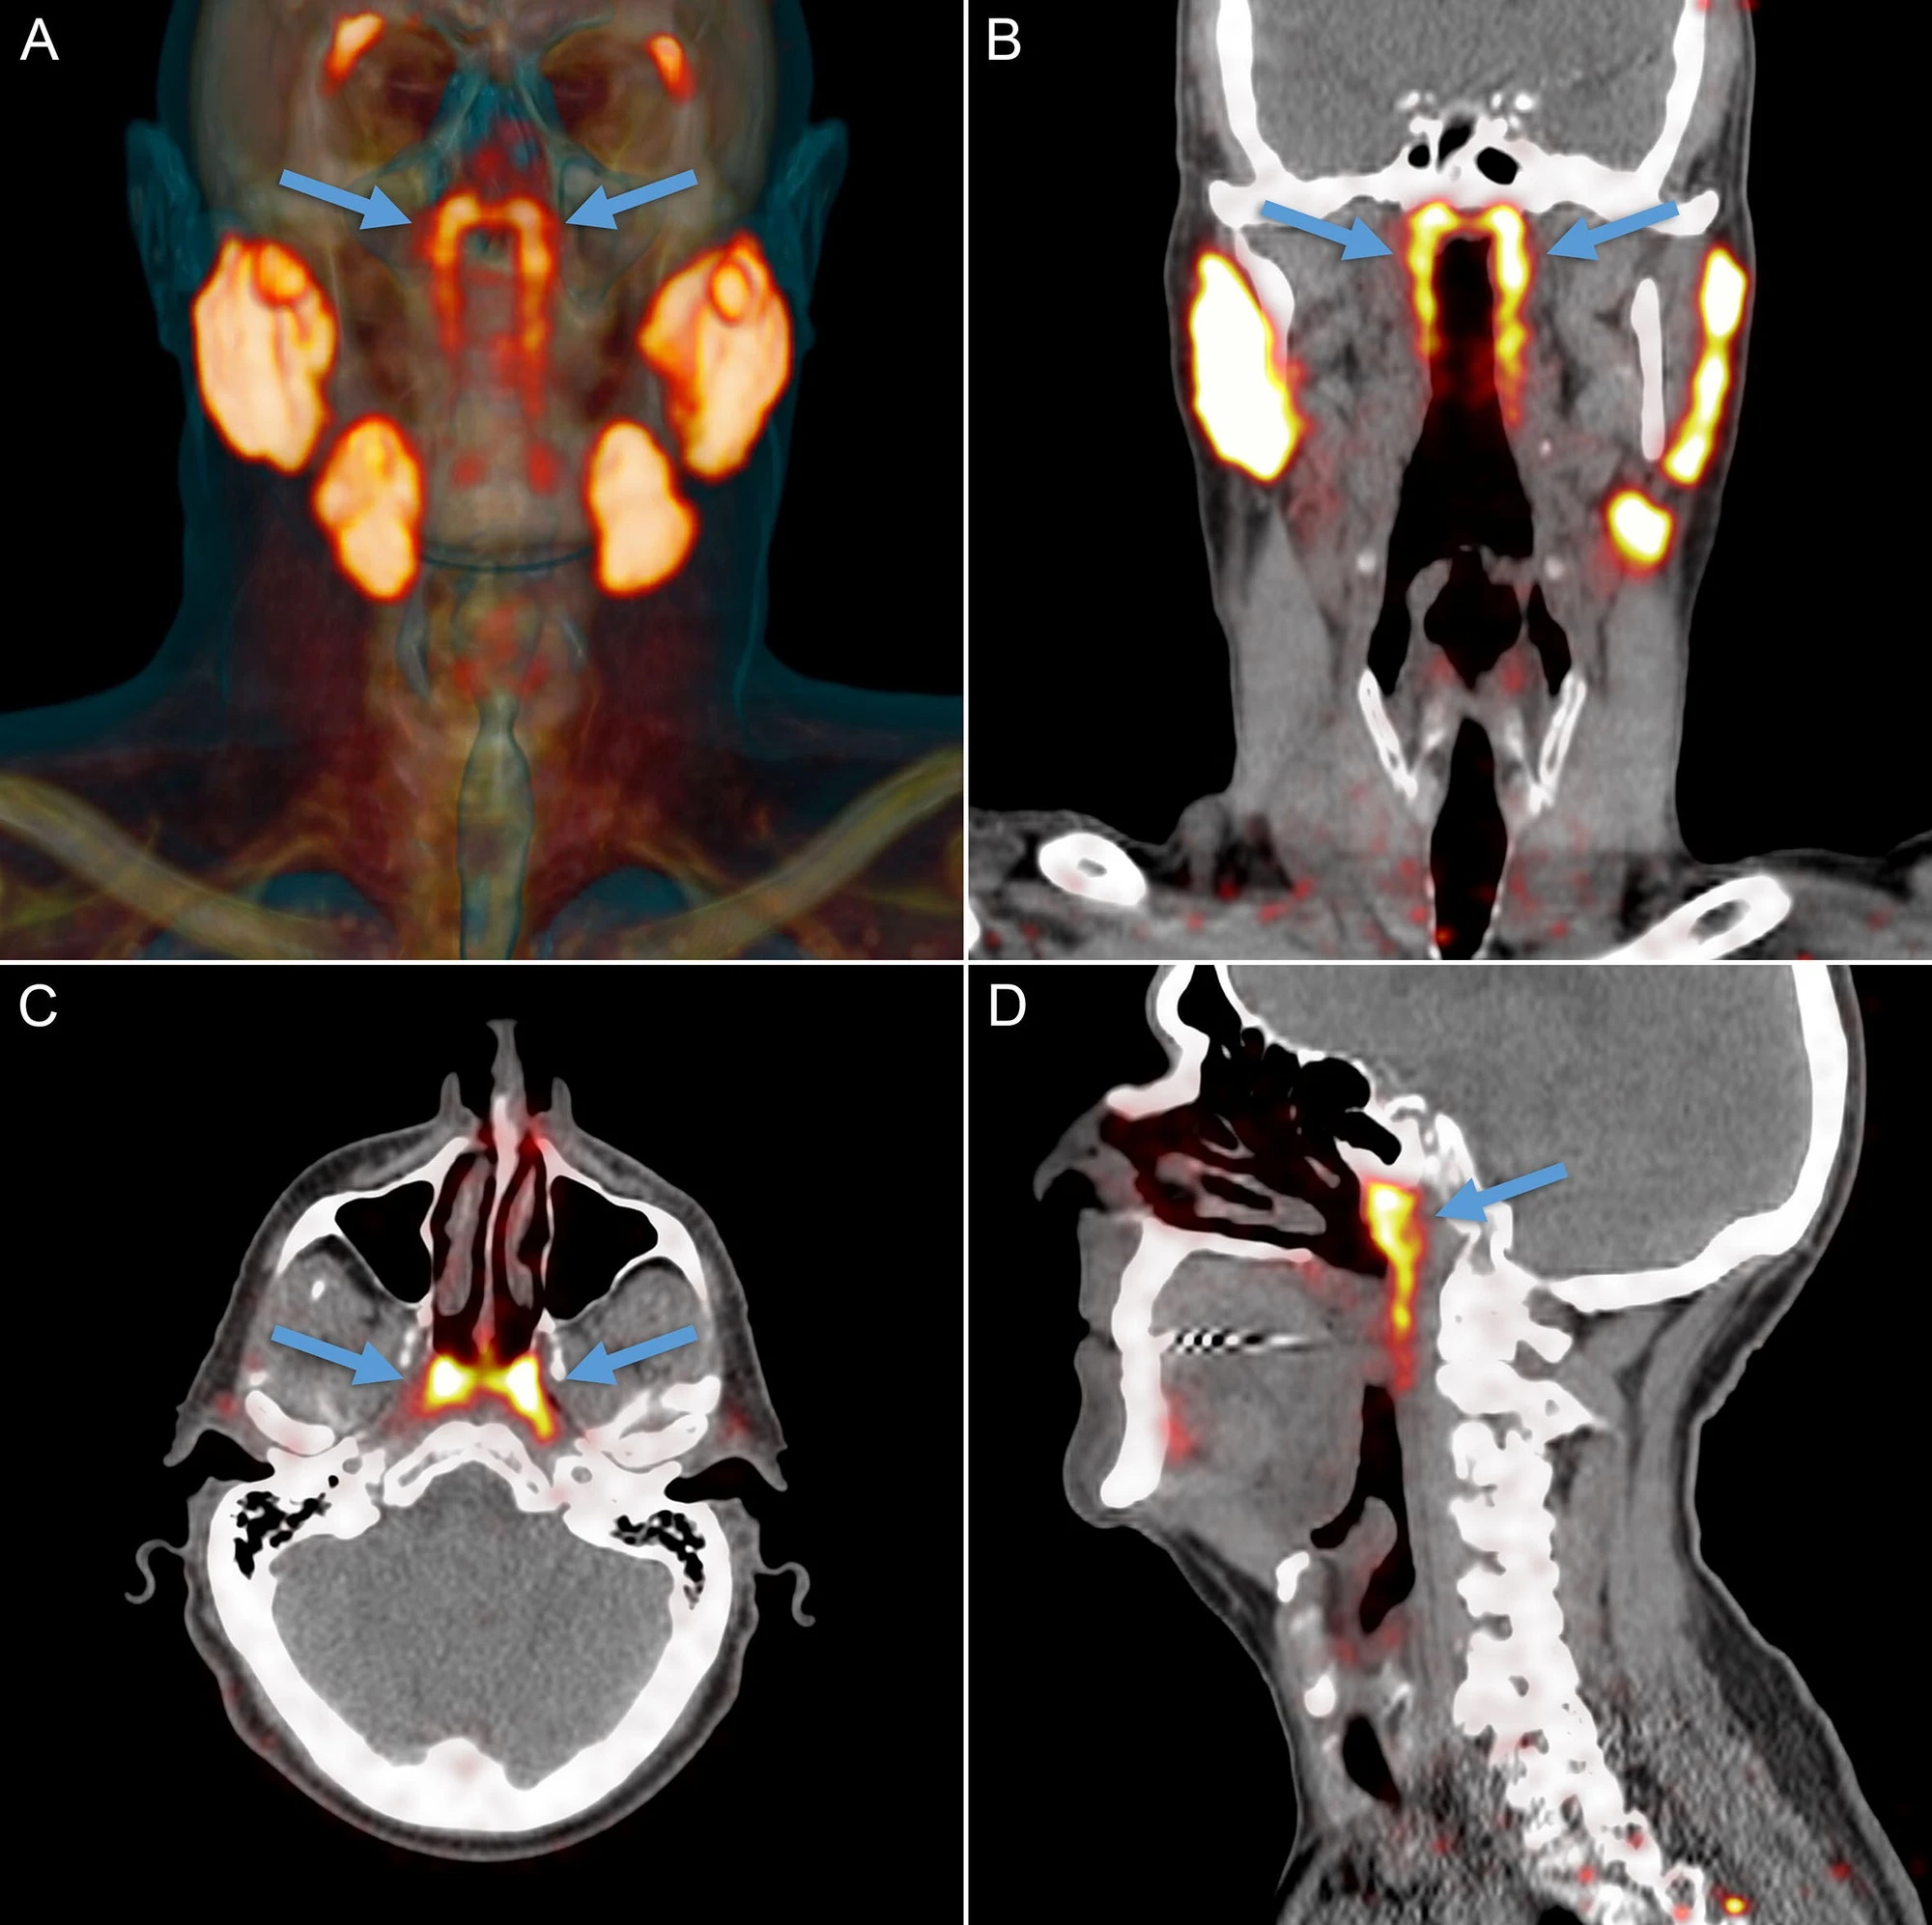

Theo PubMed, vào năm 2020, các nhà nghiên cứu Hà Lan công bố phát hiện một cặp tuyến nước bọt mới nằm ngay phía sau mũi, trong khu vực nối giữa khoang mũi và họng. Sau đó, nó đã được các chuyên gia đặt tên là tuyến nước bọt ống hầu (tubarial salivary glands). Phát hiện này lập tức làm dậy sóng truyền thông và cộng đồng khoa học vì nếu đúng, nó sẽ bổ sung vào "bản đồ" giải phẫu người vốn tự hào có 3 cặp tuyến nước bọt lớn đã được biết đến lâu nay.

Các nhà nghiên cứu Hà Lan công bố phát hiện cơ quan mới mới nằm ngay phía sau mũi, trong khu vực nối giữa khoang mũi và họng. (Ảnh: Utoronto)